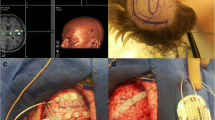

Motor cortex stimulation to relieve deafferentation pain

Therapeutic interventions to deafferentation pain also indicate a link between the pathophysiology of deafferentation pain and functions of the motor-related brain areas. Invasive and noninvasive stimulation to the M1 seem effective for ameliorating deafferentation pain. Motor cortex stimulation using surgically implanted electrodes can control poststroke pain after thalamic infarction [15], although its effects on phantom limb pain require further investigation [16]. Moreover, noninvasive stimulation to the M1 with high-frequency repetitive TMS relieves deafferentation pain, whereas low-frequency stimulation or stimulation to other brain areas does not [17, 18].

The mechanisms by which M1 stimulation reduces deafferentation pain are poorly understood. It has been suggested that “abnormal processing of nociceptive information develops at the level of deafferentation and spreads to higher levels” [15]. Together with evidence discussed in the “Deafferentation pain” section above, it seems plausible to hypothesize that reorganization of the nervous system upstream to the deafferentation level is responsible for deafferentation pain. Reorganization appears to occur in the motor and somatosensory areas after deafferentation, but the connection between those areas and the pain matrix has not been well documented. To clarify the pathophysiology of deafferentation pain, we need to know how the motor/somatosensory areas and the pain matrix interact through neural networks.